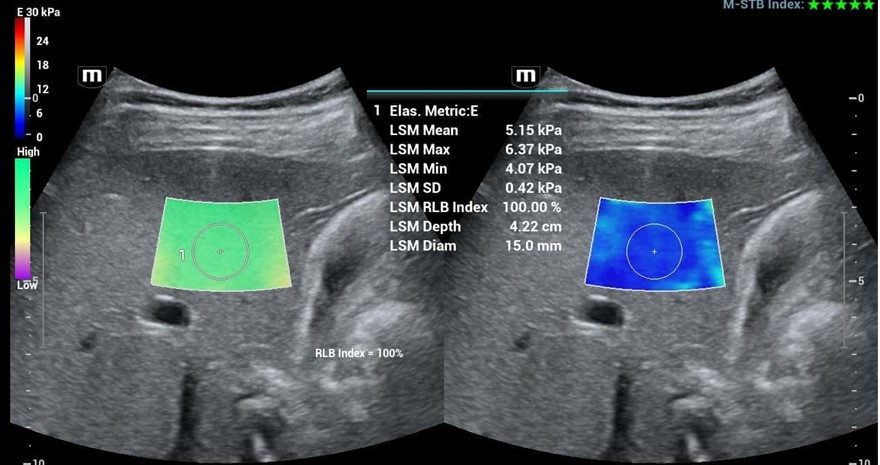

Λογισμικό Ελαστογραφίας STE shearwave Elastography (optional)

Η προσφερόμενη μονάδα υπερήχων παρέχει την πιο σύγχρονη και πρωτοποριακή απεικονιστική τεχνική Shearwave Elastography STE για την μη επεμβατική ιστική μελέτη επιφανειακών και ενδοκοιλιακών οργάνων. Διαθέτει διπλή και ταυτόχρονη απεικόνιση (Real Time) 2D & 2D + ελαστογραφία shearwave με χρωματική κωδικοποίηση των ιστών (προς επιλογή διαφορους ελαστογραφικούς χάρτες). Η μέθοδος χρησιμοποιείται για την μελέτη αλλοιώσεων σε επιφανειακές και εν τω βάθει δομές όπως στον προστάτη, μικρά όργανα άνω κάτω κοιλία κλπ. Η υπερηχογραφική Ελαστογραφία παρέχει στον κλινικό ιατρό πληροφορίες υψηλής ευαισθησίας και ειδικότητας για την ελαστικότητα των ιστών εφοδιάζοντάς τον με πληροφορίες που τον βοηθούν στον χαρακτηρισμό και την κατηγοριοποίηση των ιστολογικών αλλοιώσεων.